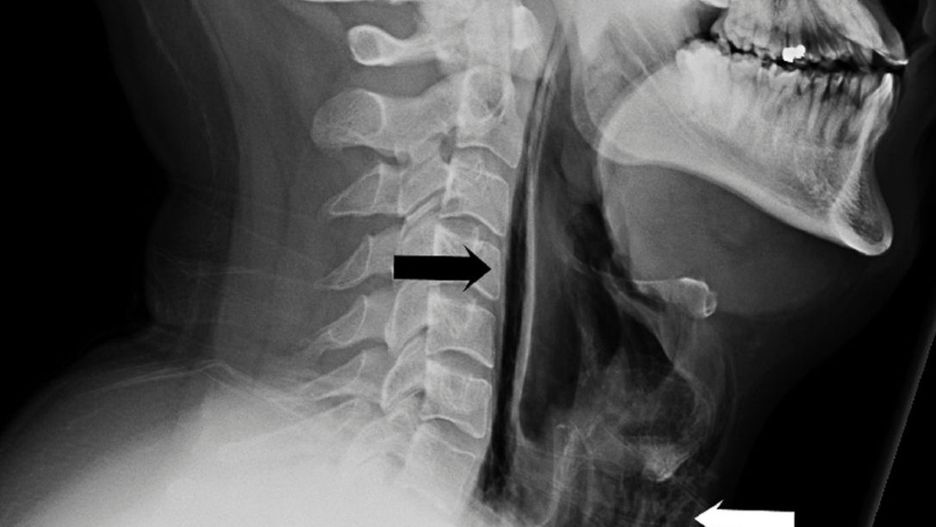

Źródło zdjęć: © BMJ | Wanding Yang, Raguwinder S Sahota, Sudip Das

Diagnozę potwierdziło zdjęcie rentgenowskie. Na prześwietleniu widać smugi powietrza. Mężczyzna próbując powstrzymać kichnięcie, w rzeczywistości wydmuchał sobie małą dziurę w gardle. - Na szczęście był to mały otwór i nie wymagał żadnego zabiegu - powiedział dr Wanding Yang, autor opisu przypadku Brytyjczyka.